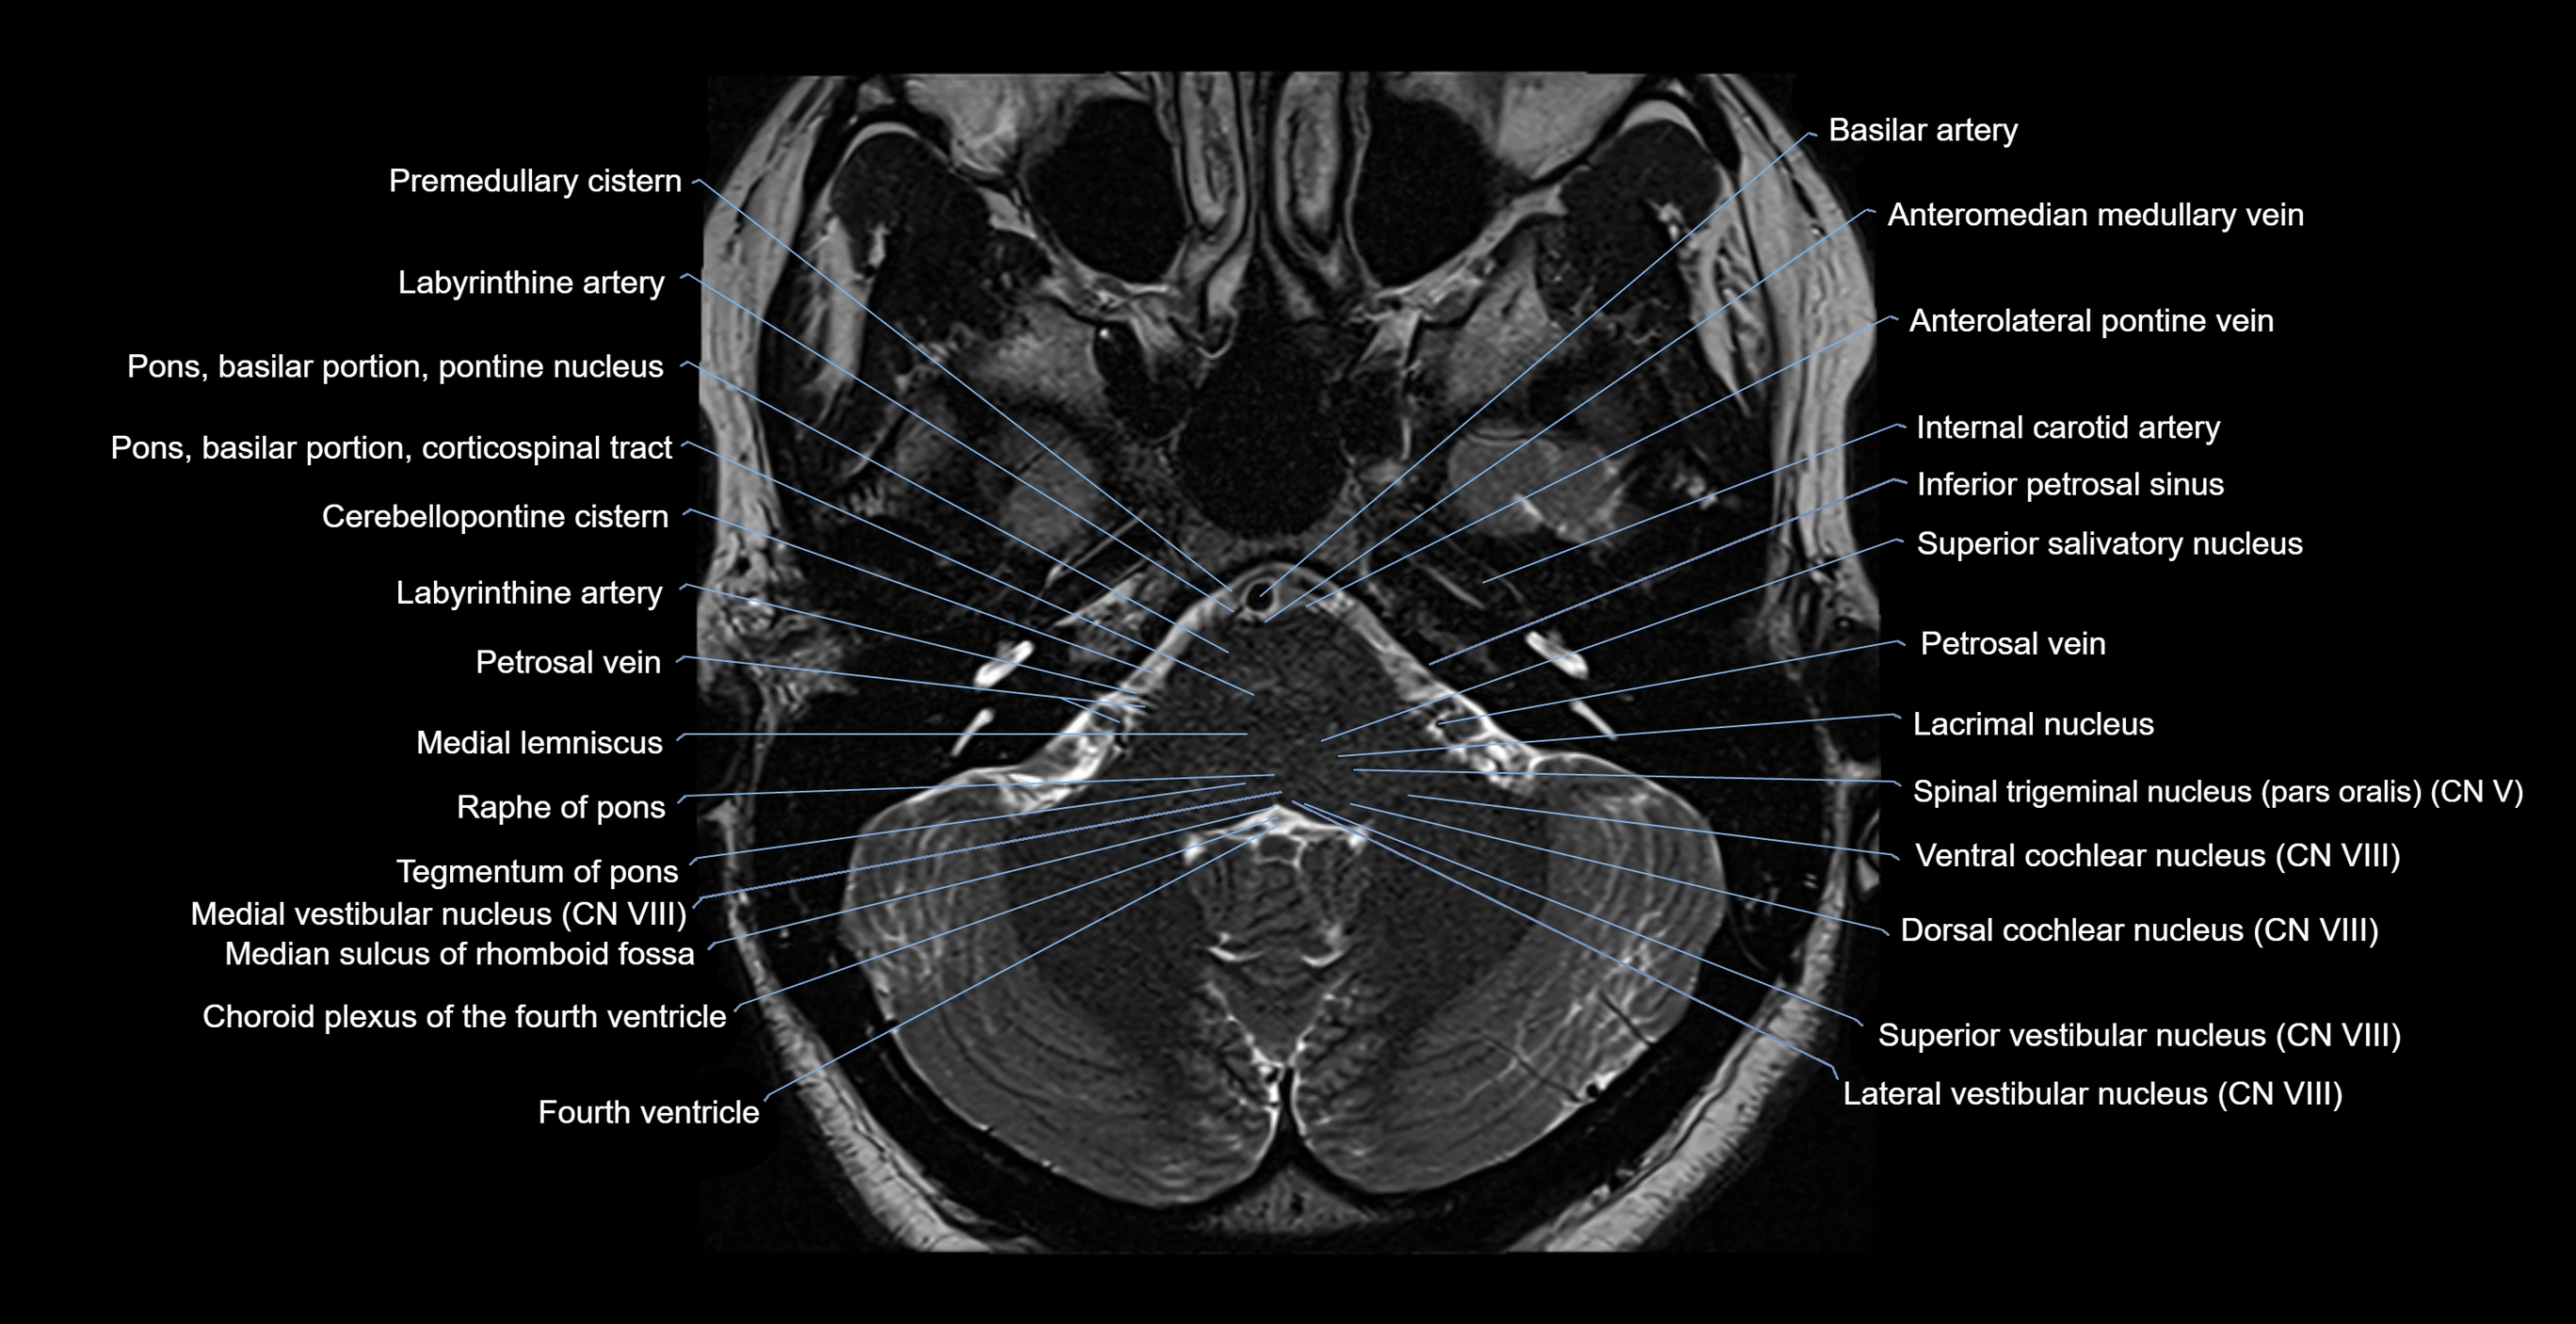

- Cerebellopontine cistern

- Dorsal cochlear nucleus

- Fourth ventricle

- Inferior petrosal sinus

- Labyrinthine artery

- Lacrimal nucleus

- Lateral vestibular nucleus

- Medial lemniscus

- Medial vestibular nucleus

- Median sulcus of rhomboid fossa

- Petrosal vein

- Pons (basilar portion)

- Pontine nucleus

- Premedullary cistern

- Raphe of pons

- Superior salivatory nucleus

- Superior vestibular nucleus

- Tegmentum of pons

- Ventral cochlear nucleus